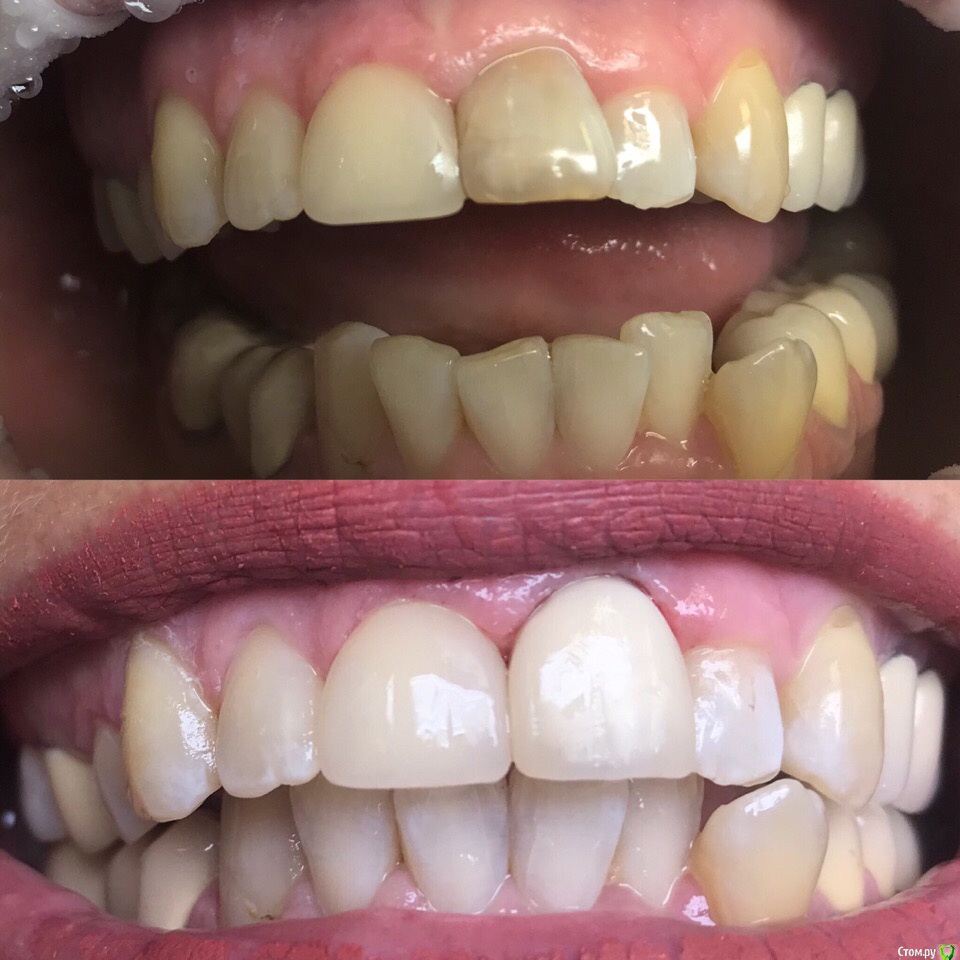

1586Doc Опубликовано 27 июля, 2019 Автор Поделиться Опубликовано 27 июля, 2019 21 реставрация Ссылка на комментарий